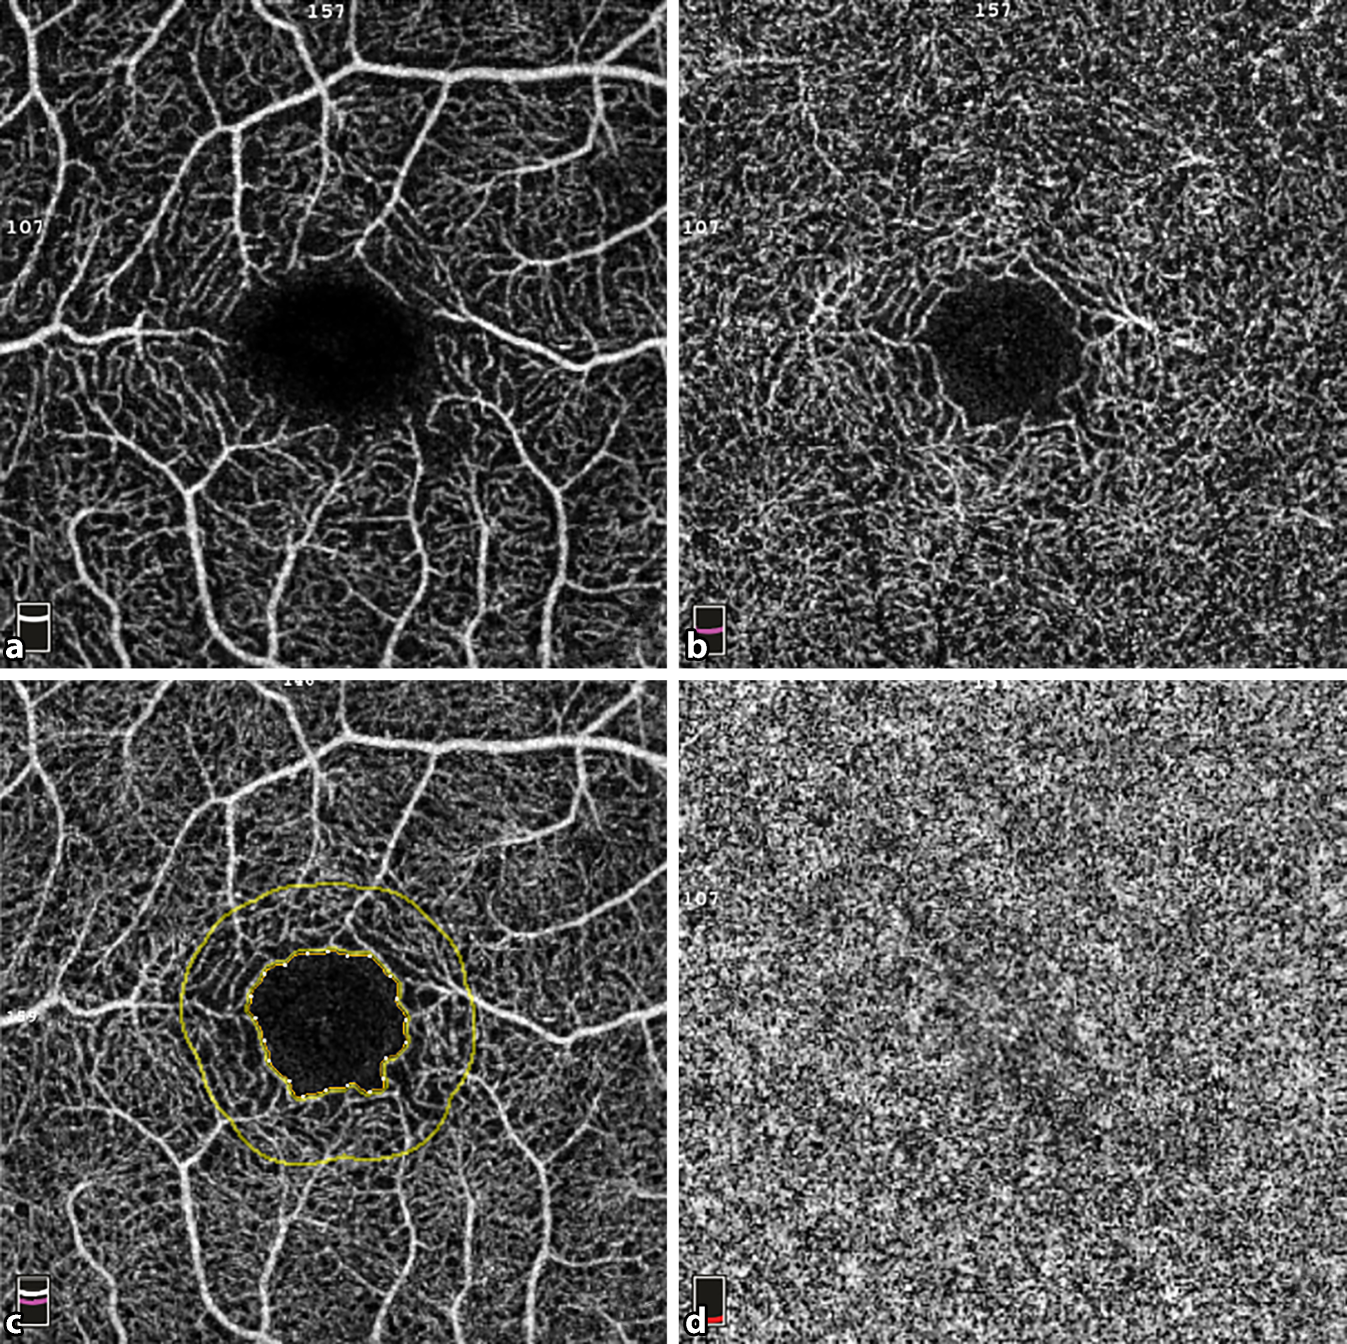

Abb. 3

En-face-Darstellung der untersuchten Netzhautschichten und der fovealen avaskulären Zone (FAZ) eines 3 × 3 mm2 OCTA-Scans der zentralen Makula eines Studienpatienten. a SCP, b DCP, c FAZ (gelber Kreis mit Punkten) und Region der perifoveolaren Kapillaren (gelber Kreis), d CC

Bild vergrößern

Der Parameter Flussdichte (FD) gibt das Verhältnis von hellen Pixeln zur Gesamtzahl der Pixel pro Scan an und wird für den Gesamtscan („whole en face“) als auch für Subregionen innerhalb des Scans in Prozent angegeben. Der interne Segmentierungsalgorithmus unterscheidet automatisch zwischen verschiedenen retinalen Schichten und Subregionen innerhalb des Gesamtscans. Diese wurden im Rahmen der Auswertung überprüft. Die Grenzen der FAZ werden durch die integrierte Gerätesoftware automatisiert innerhalb der Whole-en-face-Scans gesetzt. Bei fehlerhafter Segmentierung der FAZ kann eine manuelle Korrektur erfolgen.

Insgesamt wurden in den Bereichen des SCP, des DCP und der CC jeweils 11 Sektoren (Gesamtbild mit je oberer und unterer Hemisphäre, Fovea, Parafovea mit Untersektoren) sowie 5 Parameter der FAZ extrahiert und analysiert. Die FAZ-Parameter umfassten die Fläche der FAZ, ihren Durchmesser, den Azirkularitätsindex („acircularity index“ [ACI]) und die Dichte sowie Länge der Kapillaren der Perifoveolarregion (FD-300) ([11]; Abb. 3). Der ACI beschreibt, inwieweit die Morphologie der FAZ der Symmetrie eines perfekten Kreises entspricht, wobei ein Wert von 1,0 einen perfekten Kreis darstellt [13]. Die FD-300 umfasst die Gefäße in einem 300 µm breiten Rand um die äußere Grenze der FAZ [14].